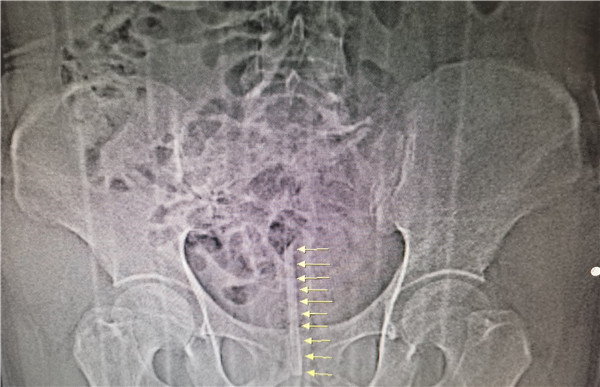

患者为一48岁男子,自诉因排尿不畅拟自行疏通,将一温度计塞入尿道,结果在“疏通”过程中温度计不慎折断,其中一截卡在尿道里面。经2天喝水排尿冲洗,无法自行排出,并渐出现血尿、尿失禁等症状。男子遂就诊于我院泌尿外科门诊,付德来副主任医师了解情况后,考虑膀胱尿道异物,需紧急处理。付医生通过急诊通道为患者完善术前相关检查,同时联系病房,准备急诊手术。经CT检查显示膀胱残留温度计断端位于膀胱内。

手术在膀胱镜下实施,具体由付德来副主任医师、唐骁爽主治医师操作,并得到了王莉主管护师、姚媚媚护师、王清园护师的密切配合。术中见温度计断端锐利,尿道局部粘膜已划伤出血。经过反复尝试并随机应变不断调整手术思路和策略,顺利将体温计断端导入膀胱镜鞘,并随膀胱镜鞘完整取出,手术历时30分钟。经测量残留温度计长约9cm,比对后确认温度计两断端对位良好,无碎块残留。

据了解,患者所用温度计为红水玻璃棒温度计,全长约30cm,直径约6.2mm,明显区别于常规的体温计。经查阅资料,红水玻璃棒温度计以煤油为工作介质,无重金属危害,这对患者来说也算是不幸中的万幸。